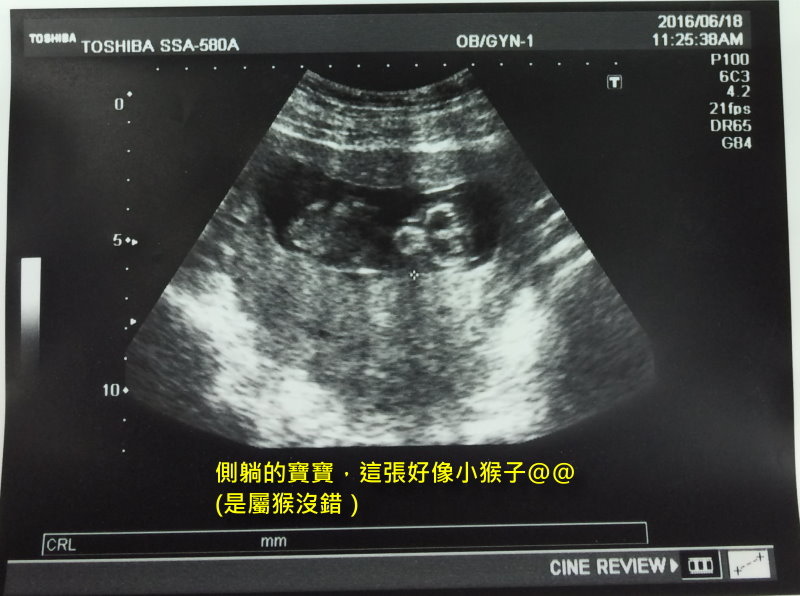

每次去產檢都會照超音波,可以看到寶寶的大小、判讀心跳聲

第一次看到胎兒落在子宮中間、第一次聽到心跳聲,那種確定寶寶就在腹中的感覺讓人感到十分興奮

孕期中的辛苦彷彿被打氣加油了然後而不覺得累~

Lulu 發表在 痞客邦 留言(0) 人氣(7,209)